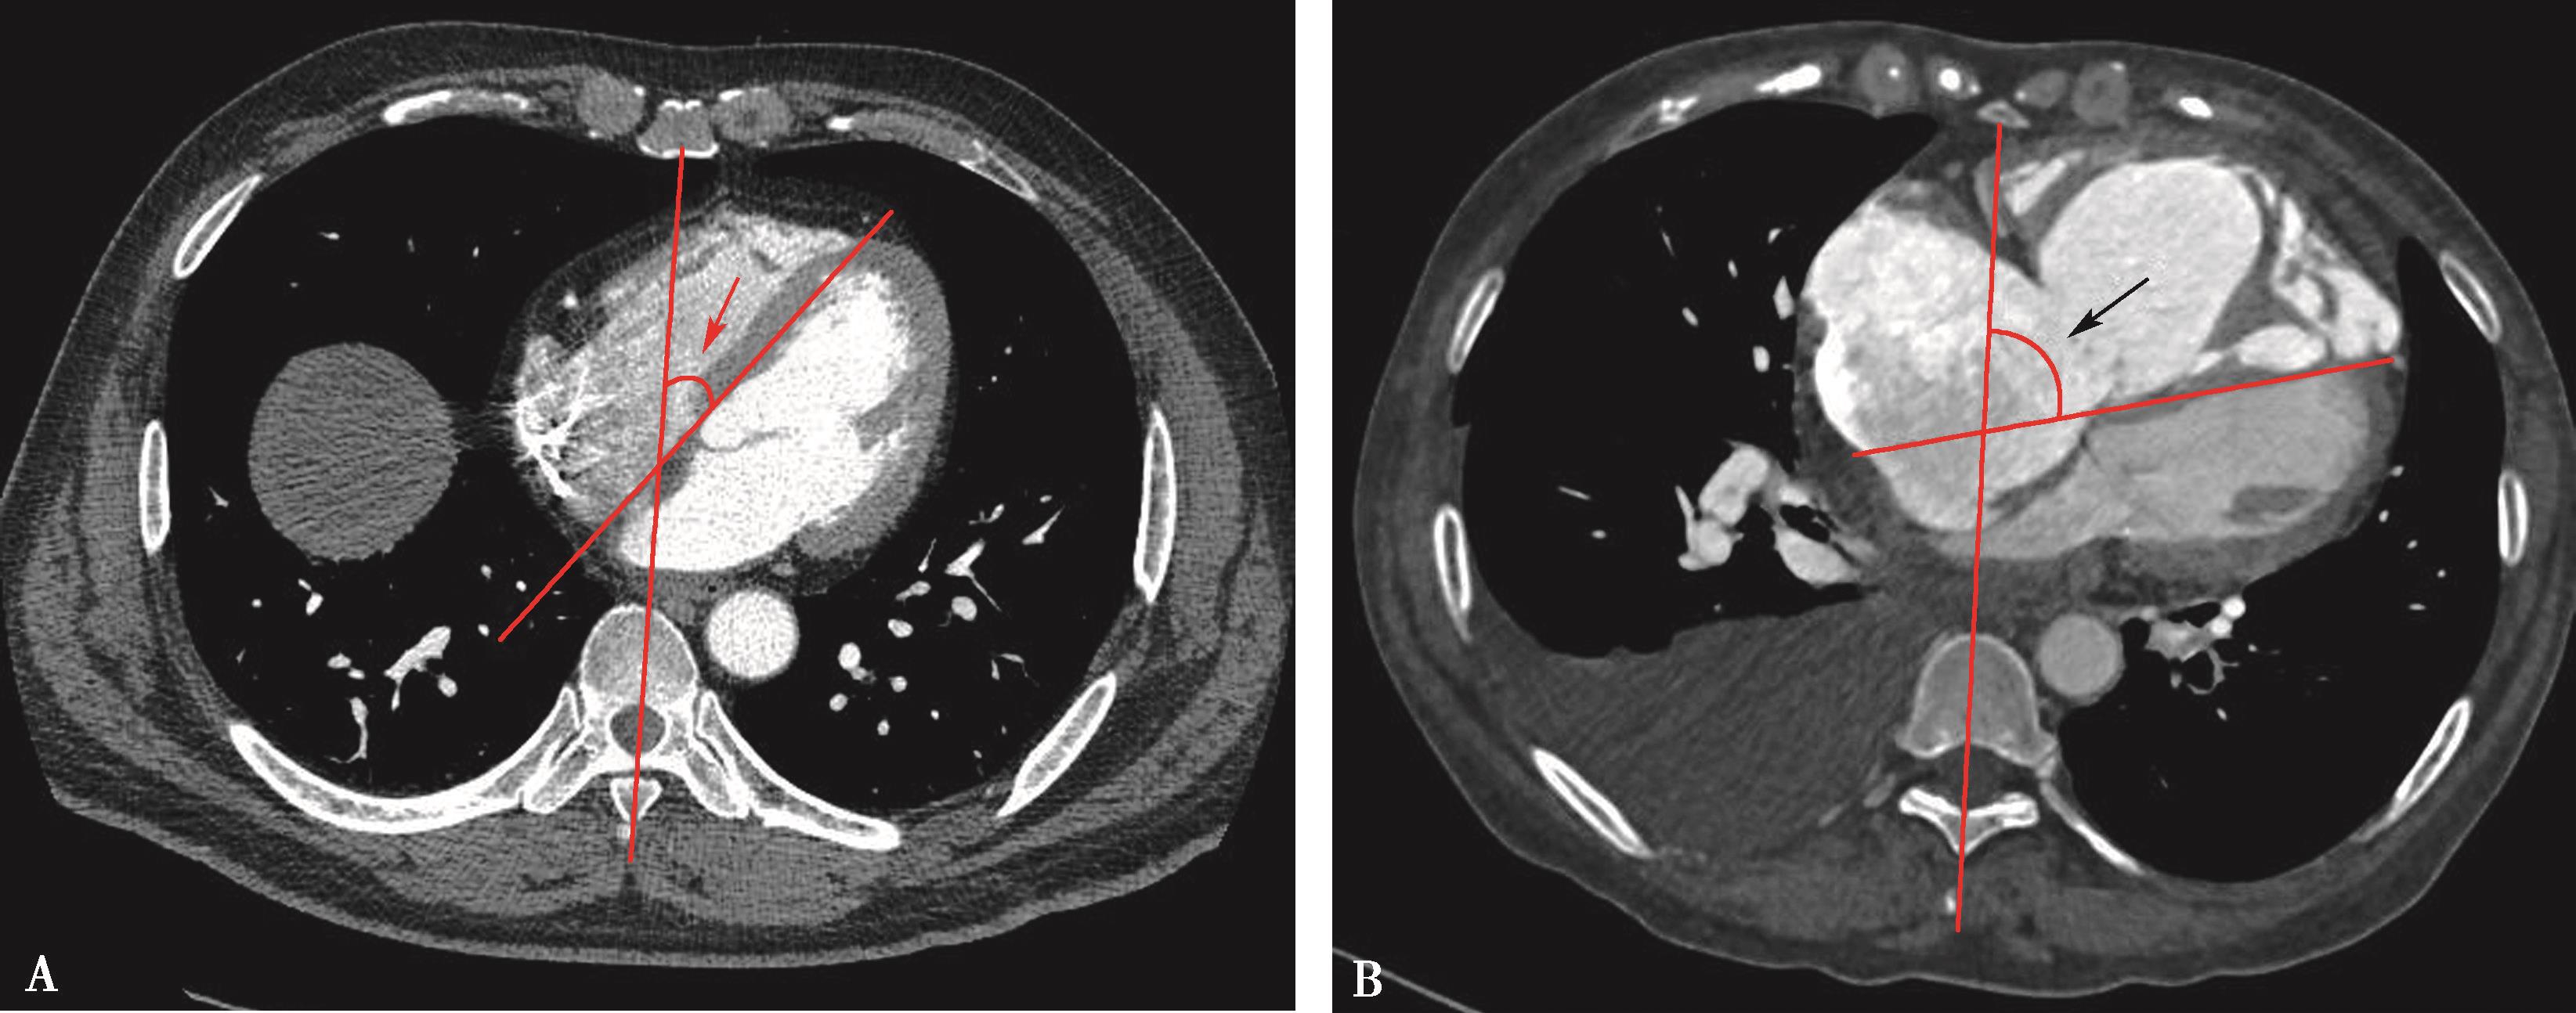

(三)多排螺旋CT右心功能评价

1.右心室增大

横断像心室最大层面测量左右心室最大横径(图8-3-10),正常心脏右心室横径:左心室横径<1,(a∶b<1),室间隔居中(红色↑)。右心室增大,右心室横径:左心室横径>1,(a∶b>1),室间隔凸向左心室(红色↑)。

2.右心室增大心脏顺钟向转位

横断像心室间隔与纵轴夹角可以反映右心室增大;由于右心室增大,心脏顺钟向转位,室间隔与纵轴夹角增大(图8-3-11)。

图8-3-10 横断图像

A.正常心脏,a∶b<1; B.右心室增大,a∶b>1

图8-3-11 横断图像

A.正常心脏;B.右心室增大,顺钟向转位,室间隔与纵轴夹角增大(↑)